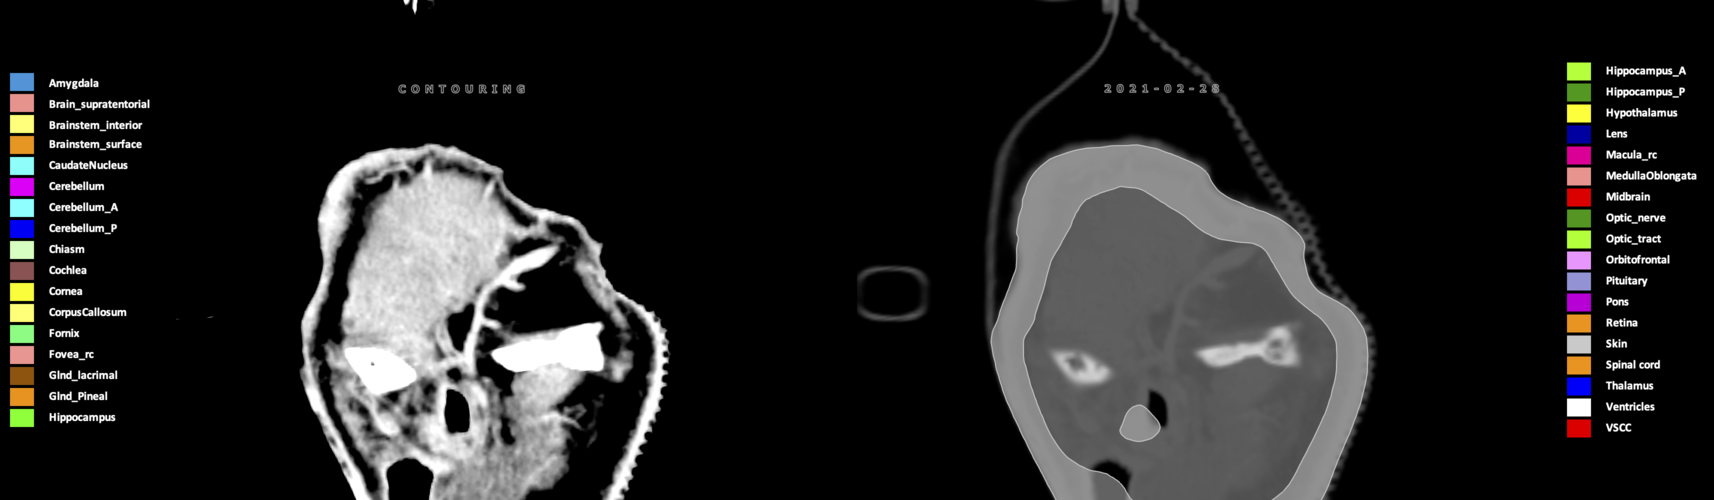

Eekers et al. have published an international neurological atlas for contouring of organs at risk in consensus with the European Particle Therapy Network (EPTN) in 2018 and an update in 2021. The purpose of this consensus atlas is to decrease inter- and intra-observer variability in delineating OARs relevant for neuro-oncology.

Included are all OARs known to be relevant for radiation-induced toxicity in neuro-oncology: brain, brainstem (midbrain, pons, medulla oblongata), chiasm, cerebellum (anterior & posterior), cochlea, cornea, hippocampus (anterior & posterior), hypothalamus, lens, lacrimal gland, optic nerve, pituitary, skin, and vestibular & semicircular canals. To further facilitate research on cognition, vision and radiological changes after irradiation of the brain, potential clinically-relevant OARs are included: amygdala, caudate nucleus, cerebellum (anterior & posterior), corpus callosum, fornix, macula, optic tract, orbitofrontal cortex, periventricular space (PVS), pineal gland, and thalamus.

Three-dimensional delineation of the 25 consensus OARs for neuro-oncology are shown on CT (WW/WL 120/40, 3000/600), 3T MR images, (T1Gd, T2FLAIR 1mm) and 7T MR (MP2RAGE 0.7 mm). All are presented in transversal, sagittal and coronal view.